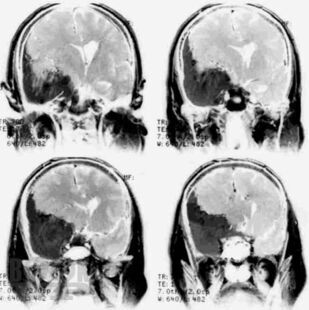

Кратко изложены этиология, особенности эпидемиологии, патогенеза, классификация и основные клинические проявления первичных опухолей головного мозга, современные принципы клиники, диагностики и оказания госпитальной помощи больным с данной патологией. Представлены алгоритмы обследования и лечения больных с наиболее часто встречающимися опухолями в зависимости от стадии течения патологического процесса.